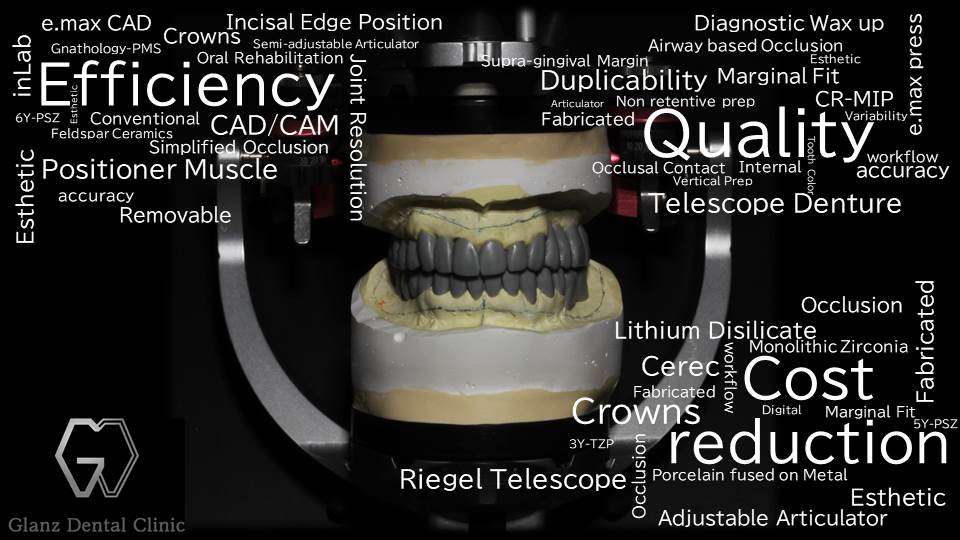

当院、グランツ歯科クリニックには、健康保険適用内のバネ式入れ歯や多数の銀歯を長年使用して、お口の中がボロボロになってしまった患者様が多数来院されています。その殆んどが欠損補綴難症例ですが、難症例な患者様ほど、ジルコニア セラミックスやインプラント、テレスコープをコンビネーションさせた最新式のテレスコープ義歯を用いた入れ歯の専門治療が非常に有効です。

セラミックスとインプラントを組み合わせたテレスコープ義歯の専門治療が受けられるのは「グランツ歯科クリニック」です。

当院には「ジルコニア セラミックス」や「二ケイ酸リチウム ガラスセラミックス」を代表とした各種セラミックスの他、インプラントやテレスコープを用いた全顎補綴の長期症例が多数あります。既に埋入してある昔のインプラントも抜かずに活用できる場合がありますので、銀歯や入れ歯、インプラントでお悩みの方は是非、グランツ歯科クリニックに御相談下さい。